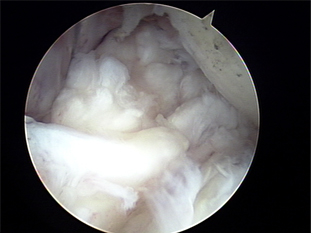

4. 수술적 치료 : 관절경으로 수술함.

외측 상과염 수술 후